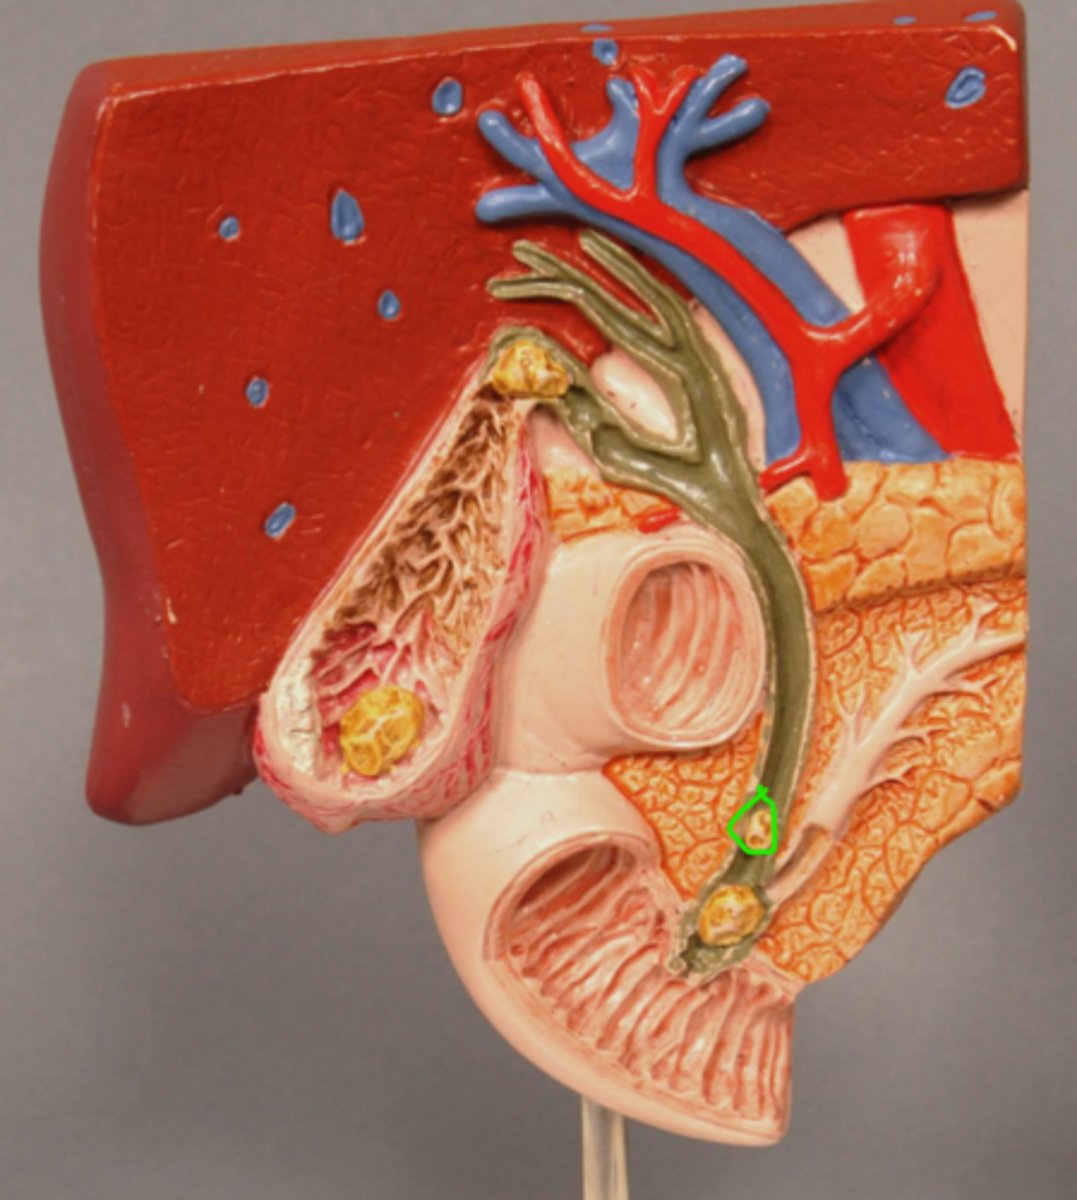

Gallstone in Bile Duct

Gallstone in Ampulla of Vater